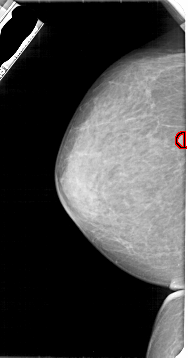

A_1947_1.LEFT_MLO

LEFT_MLO LINES 5491 PIXELS_PER_LINE 2761 BITS_PER_PIXEL 12 RESOLUTION 43.5 OVERLAY

FILE: A_1947_1.LEFT_MLO.OVERLAY

TOTAL_ABNORMALITIES 1

ABNORMALITY 1

LESION_TYPE MASS SHAPE ROUND MARGINS CIRCUMSCRIBED

ASSESSMENT 3

SUBTLETY 4

PATHOLOGY BENIGN

TOTAL_OUTLINES 1

BOUNDARY